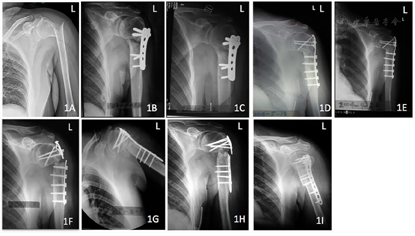

入院后,左肱骨正位X线片提示:左肱骨外科颈骨折,断端之间成角畸形,移位明显(图1A)。

完善相关检查和术前准备后,排除手术禁忌,于2002年9月行左肱骨近端骨折切开复位钢板内固定术。术后1年复查,断端骨折线明显,少量骨痂生长,肱骨近端内翻畸形(图1B)。2004年2月(术后18个月)复查,患者患侧疼痛明显,X线检查提示肱骨近端内翻畸形,颈干角约122°,肱骨内侧距复位欠佳,骨折线明显(图1C)。诊断为骨不连,行翻修手术,拆除内固定并纠正复位,恢复内侧距连续性,更换三叶草型钢板。术后3个月(第1次手术后21个月)复查,X线片示:颈干角纠正(约139°),内侧骨痂生长稀疏(图1D)。术后7个月(第1次手术后25个月)复查,X线片示:复位丢失同上次复查,颈干角缩小(约135°)(图1E)。2005年8月(术后18个月,第1次手术后36个月),患者自觉左肩疼痛,复查X线片,提示骨折断端进一步内翻,颈干角缩小(约118°),三叶草型钢板断裂(图1F)。再次翻修手术,更换坚强肱骨近端锁定钢板,并采用人工骨植骨(图1G)。2006年1月(第3次手术后5个月,第2次手术后23个月,第1次手术后41个月),患者再次发生左肩肿痛,复查X线片提示骨折断端移位,人工骨吸收,肱骨近端锁定钢板于骨不连平面断裂(图1H)。第3次翻修手术更换肱骨近端锁定钢板,近端内侧自体腓骨移植支撑肱骨头(图1I)。